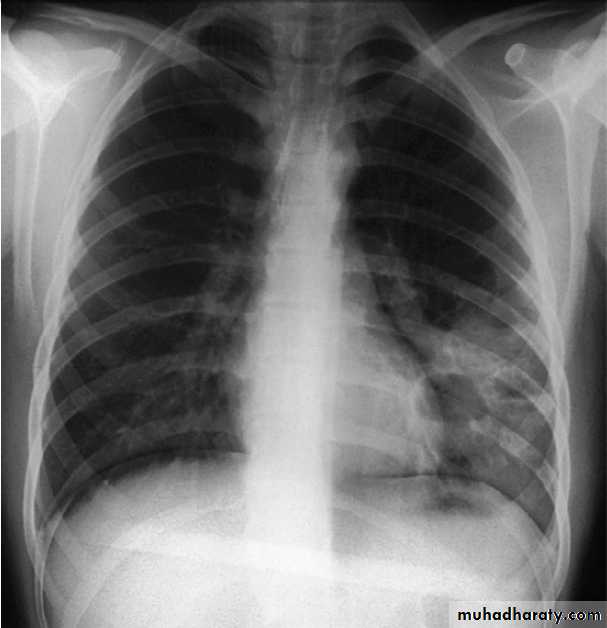

Near-drowning. Chest X-ray of a 39-year-old farmer, 2 weeks

after immersion in a polluted freshwater ditch for 5 minutes before rescue.Airspace consolidation and cavities in the left lower lobe reflect secondary

staphylococcal pneumonia and abscess formation.